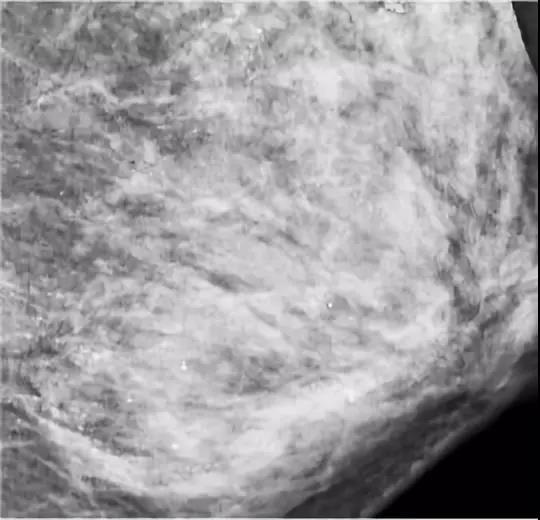

在进行乳腺钼靶X线摄影检查时,医生发现朱女士的左侧乳房布满众多细小如沙子一样、呈散在分布的钙化灶,并且无法轻易判断哪些是良性,哪些是恶性。

钼靶检查发现,朱女士乳腺里满是星星点点的钙化灶 / 武汉晚报